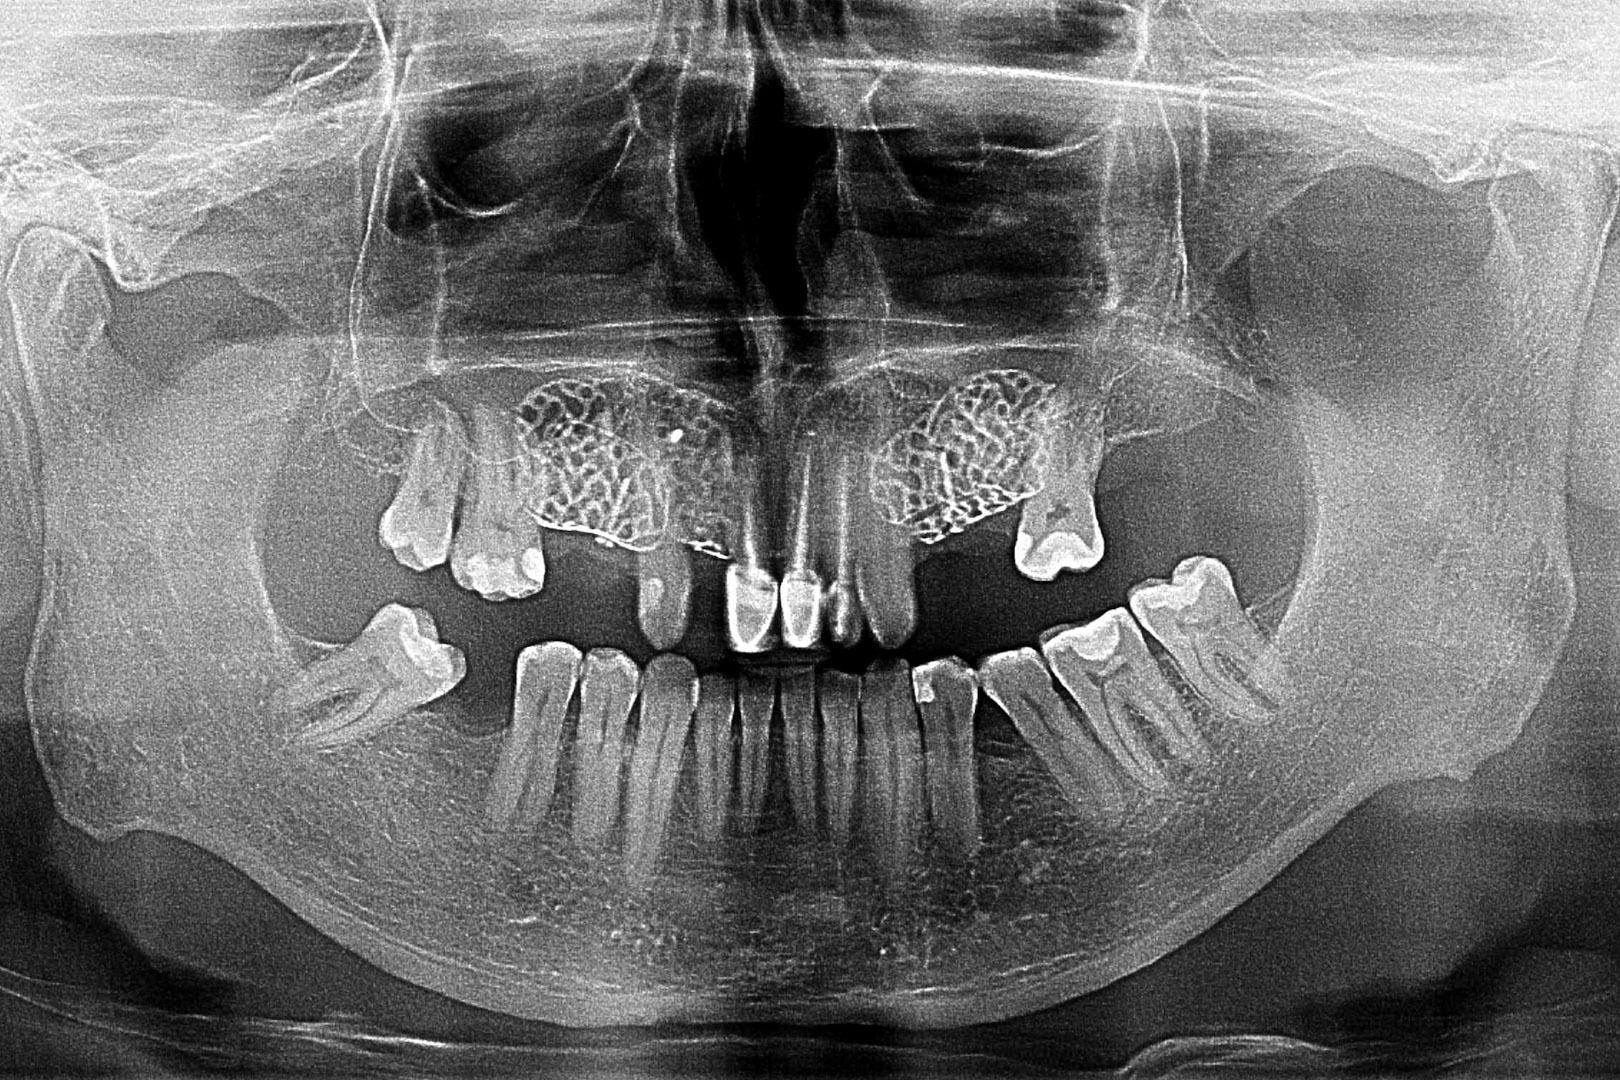

Przed podjęciem leczenia należy określić stopień zaniku kości szczęk oraz żuchwy. W tym celu przeprowadza się badanie kliniczne oraz odpowiednią diagnostykę obrazową pacjenta. Uwzględnia ona zdjęcie panoramiczne OPG jako podstawę dwuwymiarowego obrazowania podłoża kostnego oraz możliwe jest badanie tomograficzne CT lub bardziej precyzyjna tomografia stożkowa CBCT. Opcjonalnie wykorzystywana diagnostycznie tomografia pozwala na bardziej wnikliwą ocenę stopnia zaniku kości w trójwymiarowym, przestrzennym obrazie.

U pacjentów spotykamy 3 typy zaników kości wyrostka zębodołowego szczęk i żuchwy: